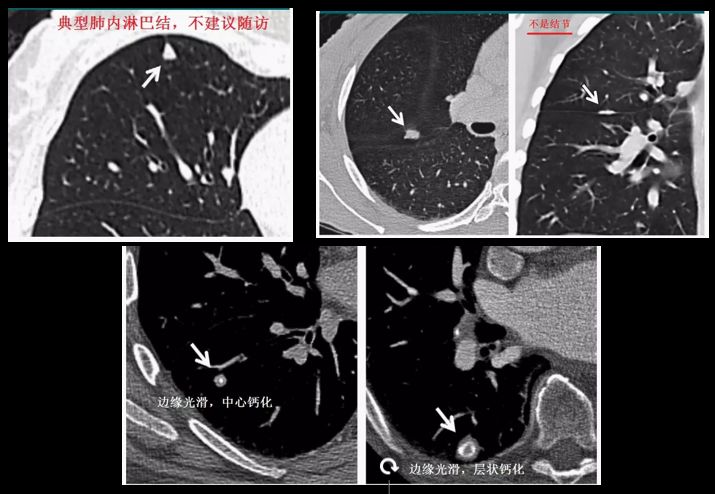

无论哪种结节类型,都有良性和恶性两种可能性。唐小军教授强调到,虽然有些结节具有明显恶性特征,但还是不能通过CT影像百分百判断结果,最准确的判断方式只有病理切片。因此,通过CT的经验大体分为以下几种性质:

炎性结节(包括非特异性炎症或特异性炎症,如结核);

肺内淋巴结;

良性肿瘤,如错构瘤;

8mm以上的结节,如果有钙化等典型的良性病变特征的,每年常规体检就可以了。